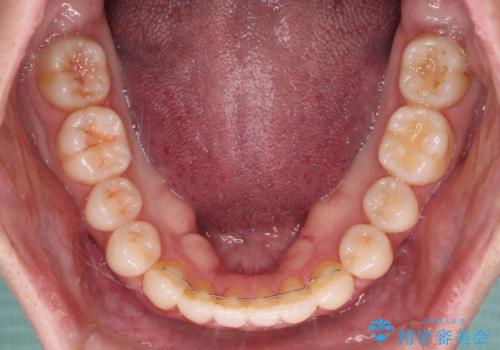

- 下唇に上の前歯が当たることを気にして来院された患者様です。

上顎の親知らずを抜去し、歯列全体を後方に移動させるとともに、IPR(歯と歯の間を削る)を行うことで口元の閉じにくさを改善していくこととしました。

咬合力が強く、マウスピースを介した咬み込みが顕著であったため、奥歯の咬みにくさやIPRのスペースが改善しにくく、治療期間が思った以上にかかってしまいました。